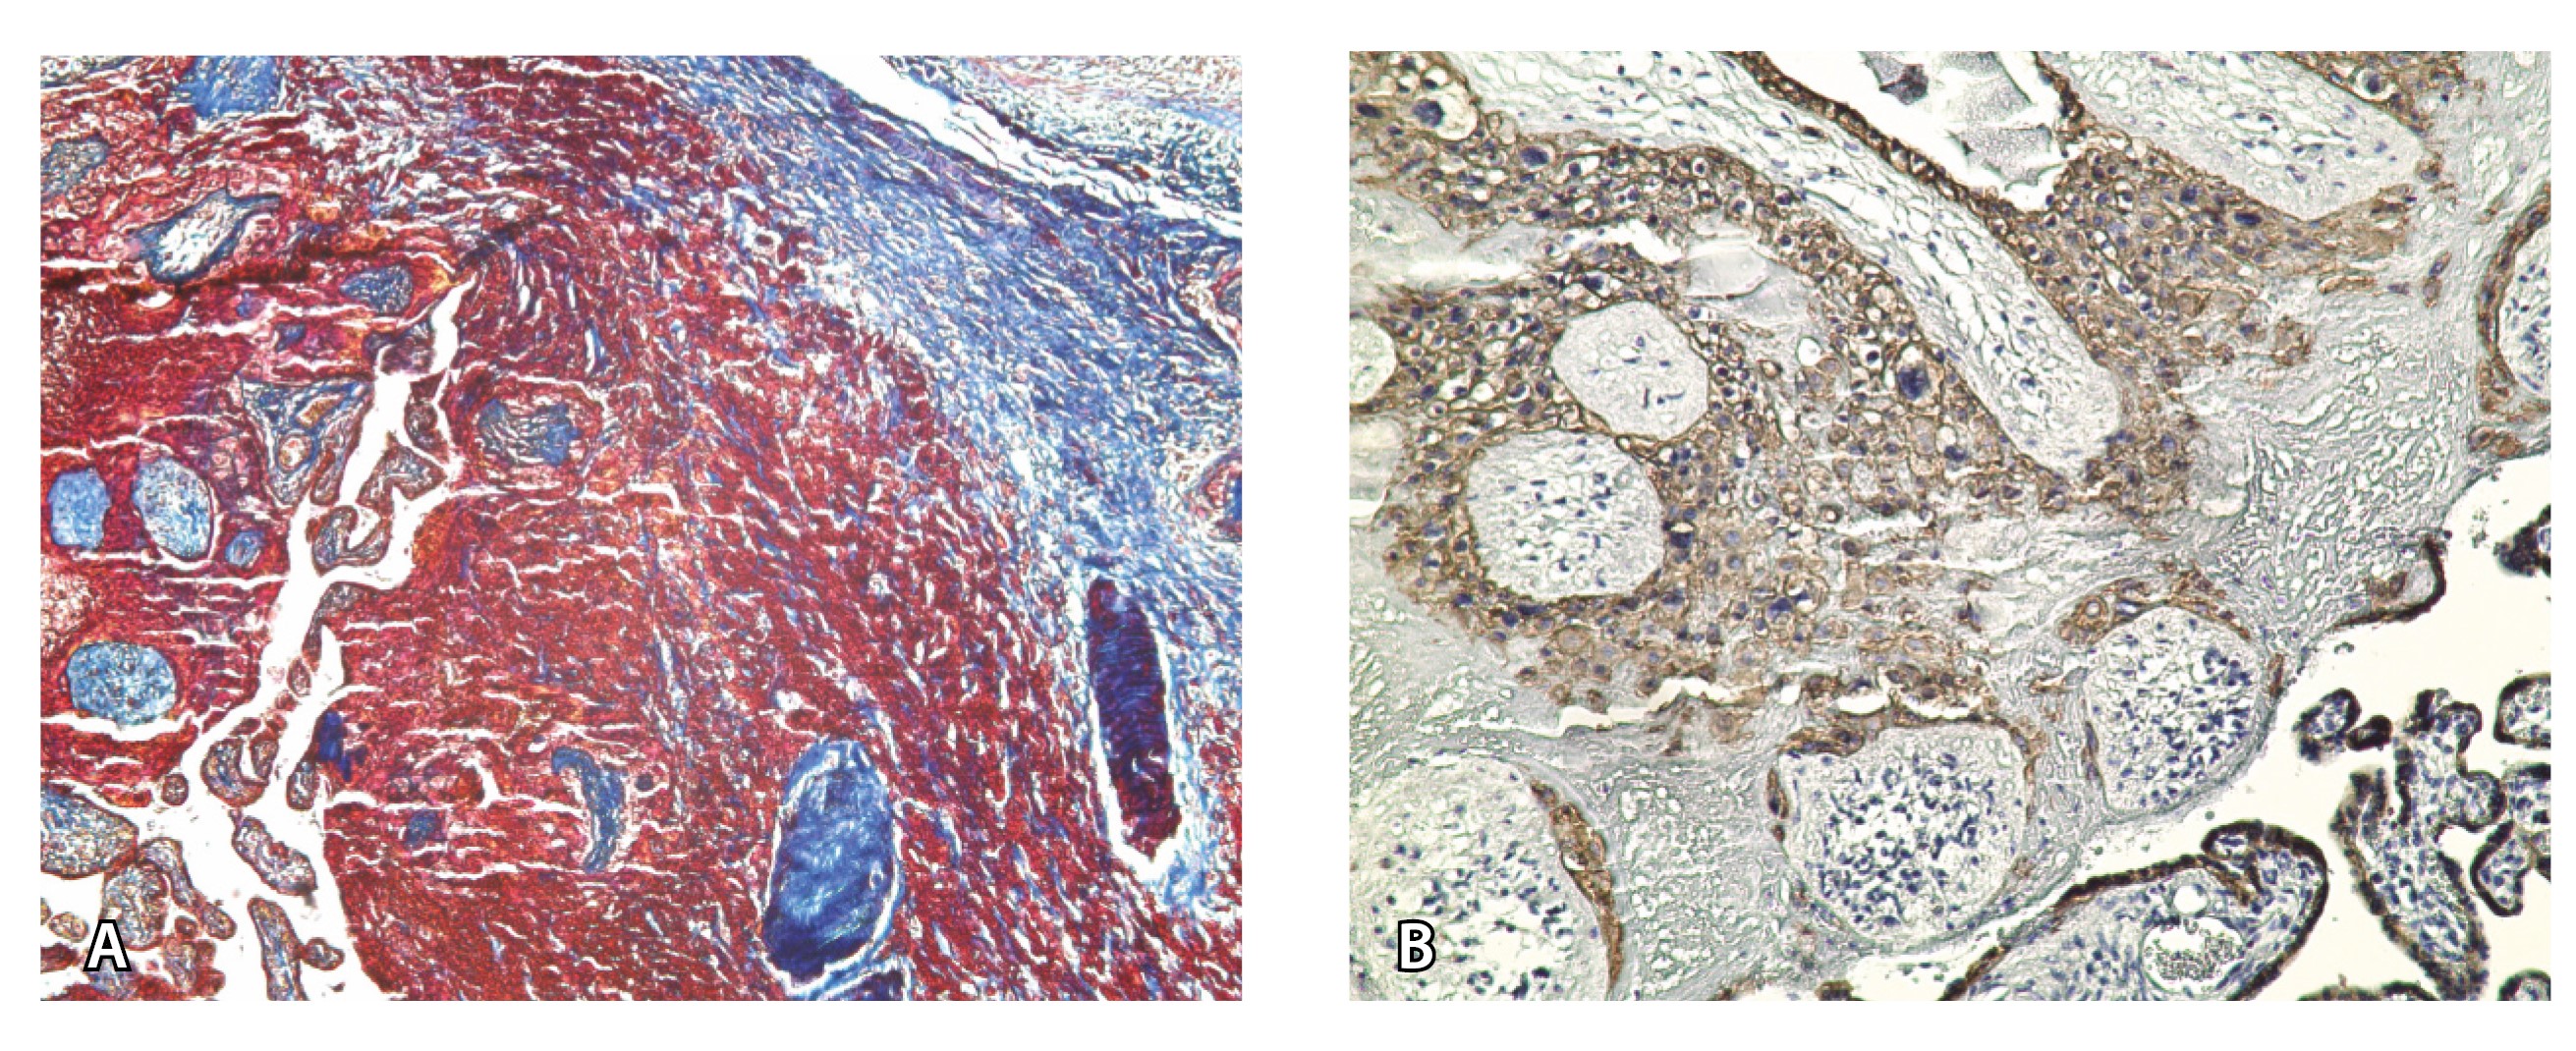

Непосредственное сравнение МР-картины с операционным материалом подтвердило, что полости с геморрагическим компонентом соответствовали ретрохориальным гематомам различной давности, чаще подострой и хронической стадий, которые состояли из гемолизированных эритроцитов, нитей фибрина сетчатого строения, а также замурованных атрофичных ворсин (рис. 5). Следовательно, констатация на МРТ фиксированных геморрагических полостей в маточно-плацентарной области отражает не гиперваскуляризацию стенки матки, а наличие ретрохориальных гематом в подострой/хронической стадии, что следует учитывать в клинической практике.

Рис. 5. Сосуды 2-го типа при гиперваскуляризации стенки матки при патологической инвазии: А – организованная ретрохориальная гематома в маточно-плацентарной области, в ее составе много инволютивных якорных ворсин (окраска по Маллори; × 100); Б – в составе гематомы видна пролиферация цитотрофобласта (иммуногистохимическое исследование, маркер цитокератин 8; × 100)